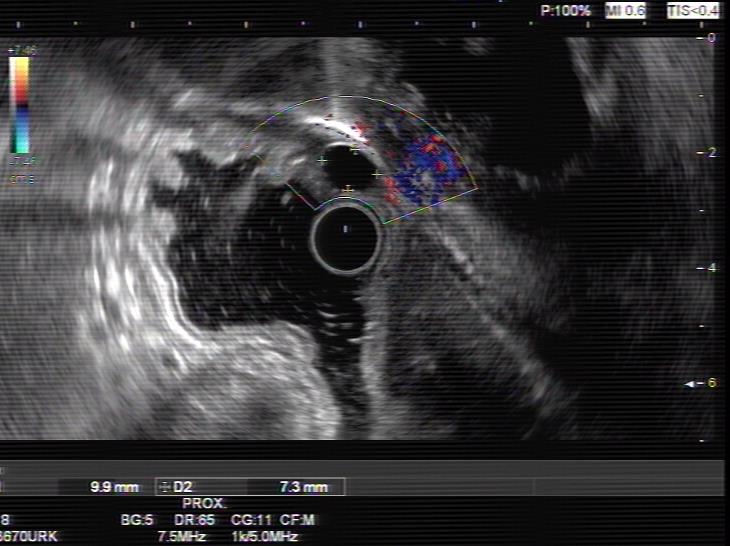

患者,66岁,女性,平素身体健康,以“发现胃肿物2年余”主诉入院,既往于外院行电子胃镜检查发现胃底隆起,直径约1.5-2.0cm,超声内镜检查考虑黏膜下来源间质瘤可能,不除外壁外病变压迫。外院CT提示胃底浆膜下囊性病变可能。患者及家属诊治心切,辗转数家医院后为求内镜下治疗遂来二附院。入院后在消化内科再次超声内镜检查,提示胃壁增生病变可能,增强CT提示胃底胃壁增厚,结合内镜检查。患者及家属强烈要求内镜下探查及病变切除术。术前在王进海主任的指导组织下,进行了专业组内及多学科讨论,与患者及家属充分沟通后,决定行内镜下切开探查及病变治疗术,必要时可行内镜-腹腔镜联合手术(LECS)。邹百仓教授带领内镜下肿瘤诊治及超级微创手术团队施行手术,术中逐层切开胃壁黏膜层及黏膜下层,暴露固有肌层,未发现胃壁病变,遂切开胃壁全层,局部腹腔探查,切口附近腹腔内似韧带组织上发现半球形隆起,表面透亮光滑,大小约1.5X1.5cm,术中请外科李军辉及袁庆攻教授会诊后确诊为囊性病变,讨论后建议可以观察或内镜切开引流,与患者家属沟通后家属强烈要求切开引流,遂用内镜切开刀切开囊肿,引流少量清亮囊液,囊肿塌瘪,观察囊肿切口及局部无出血,切除局部部分胃壁组织送检,内镜下严密关闭切口,留置胃管后,返回病房,常规对症治疗1周,患者无并发症发生,正常出院。

上腹部增强CT 超声内镜